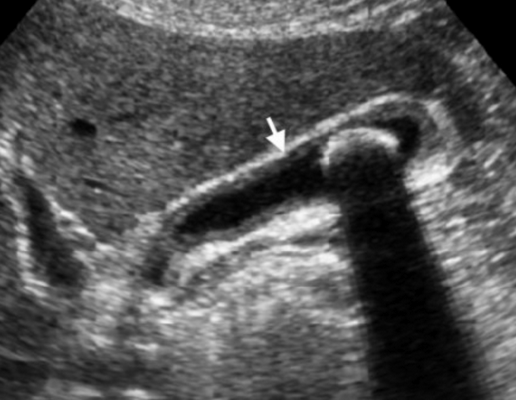

Термин хронического холецистита используют для обозначения вялотекущего воспалительного процесса с фиброзированием стенки желчного пузыря и образованием в просвете камней.

Представлен больной с хроническими болями в правом подреберье, который ежедневно воздерживался от еды с вечера. Утолщение слабо выраженное и не является физиологическим. Также визуализируются обструкция и камень. После УЗИ данному больному был поставлен диагноз — хронический холецистит.